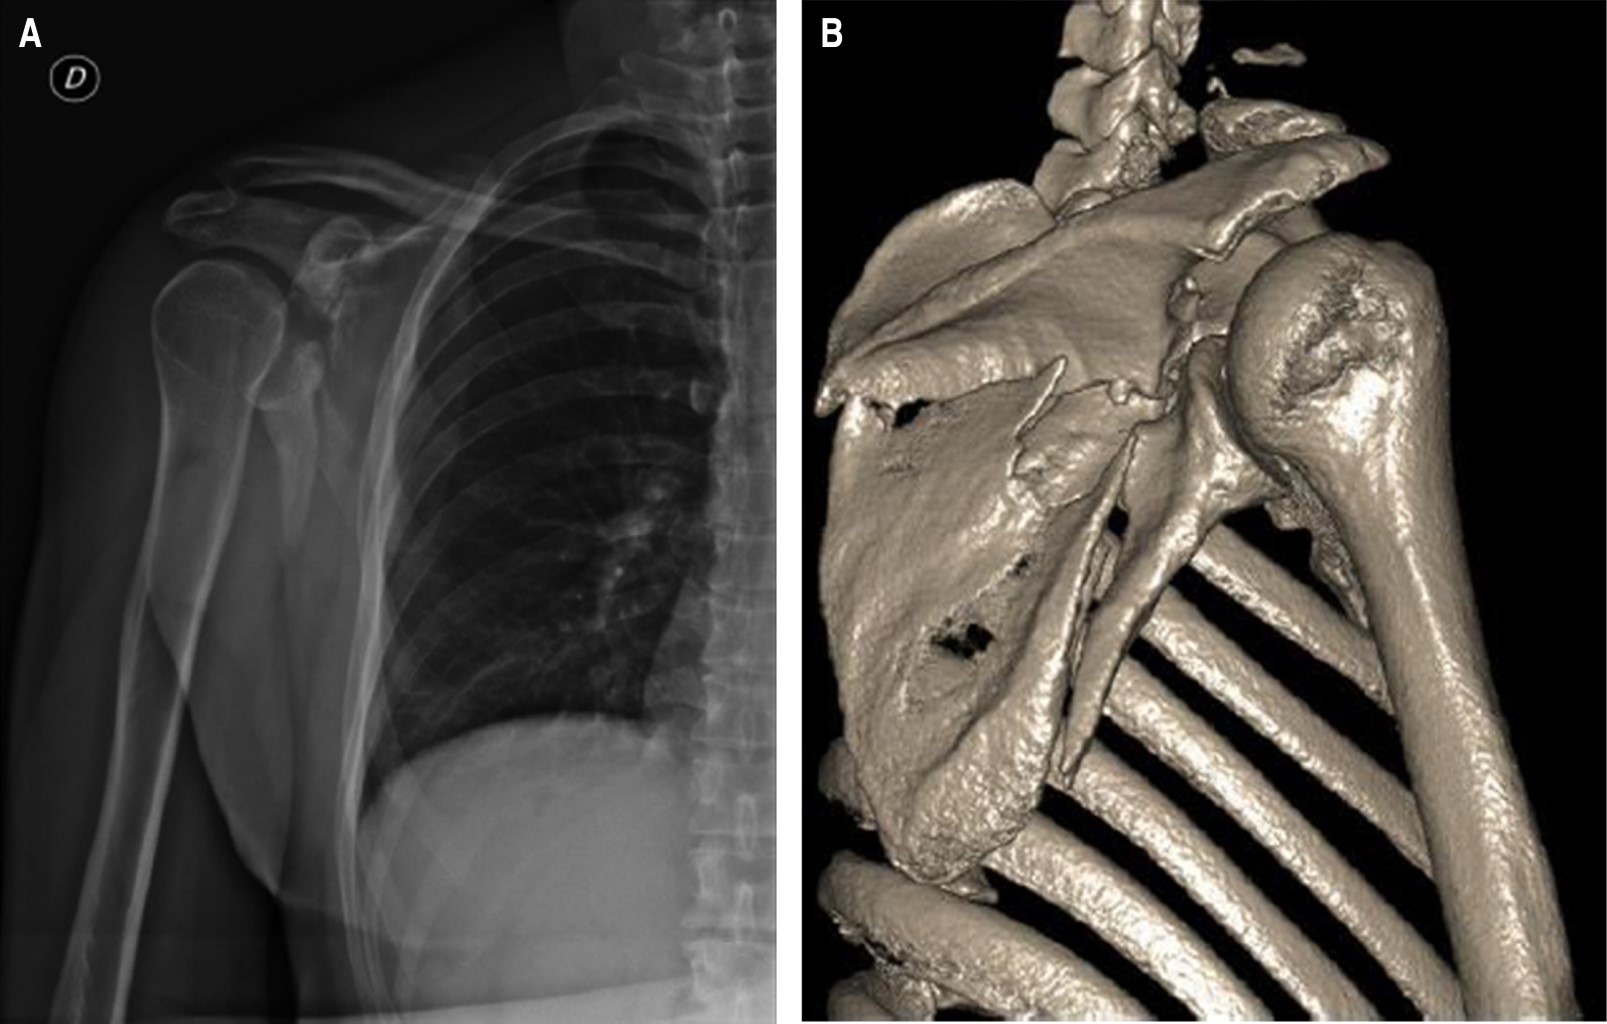

Paciente sin antecedentes patológicos diagnosticados, presentó accidente de tránsito de alta enérgica con fractura a nivel de escápula derecha (Figura 1). Fue llevado a manejo quirúrgico operatorio con reducción abierta de fractura más fijación interna. Presentó episodio de dolor intenso calificado en la escala numérica del dolor (numeric rating scale [NRS]) de 10 en zona de hombro y escápula derecha, se manejó con morfina 8 mg, diclofenaco 75 mg, dipirona 2 g en forma endovenosa, con mejora de dolor durante 30 minutos. Refirió recurrencia de dolor a intensidad en NRS de 10.

Figura 1